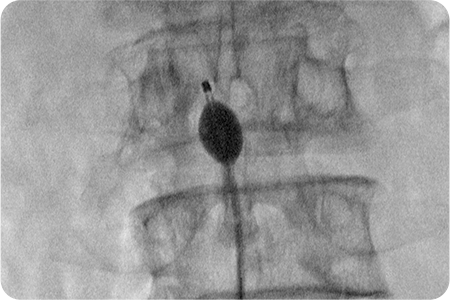

풍선확장술

풍선이 내장된 특수 카테터를 척추에 삽입하여

좁아진 척추관의 폭을 넓히는 치료법입니다.

신경에 직접 유착방지제와 항염증제를 주입해 통증을 줄이고,

풍선을 부풀려 신경 주변 공간을 넓혀 척추관 협착증에 효과적입니다.

풍선확장술은 꼬리뼈를 통해 특수 카테터를 삽입해 풍선을 부풀려 신경 주변 공간을 직접 넓히는 최신 비수술적 시술입니다.

풍선으로 눌린 조직을 밀어내어 신경 압박을 완화하고, 약물을 정확히 병변 부위에 전달해 통증을 줄이는 장점이 있습니다.

풍선확장술 치료과정